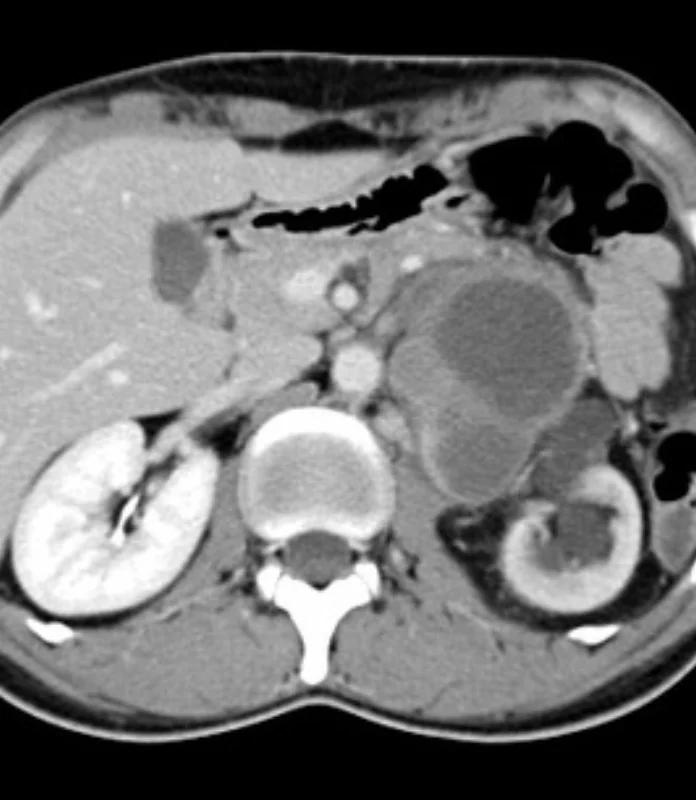

Retroperitoneal tumors develop in the space behind the abdominal organs, close to vital structures such as major blood vessels, kidneys, nerves, and intestines. Due to their location, these tumors often grow silently and are detected at an advanced stage. Under the care of Dr. Anuj Suketu, patients receive specialized evaluation and carefully planned surgery for retroperitoneal tumors. Each procedure is performed with precision, aiming for complete tumor removal while preserving nearby organs and maintaining quality of life.

Retroperitoneal tumour surgery involves the surgical removal of tumors arising in the retroperitoneal space, the area behind the abdominal lining.

Surgical planning is based on detailed imaging studies and multidisciplinary evaluation to ensure safe and effective treatment.